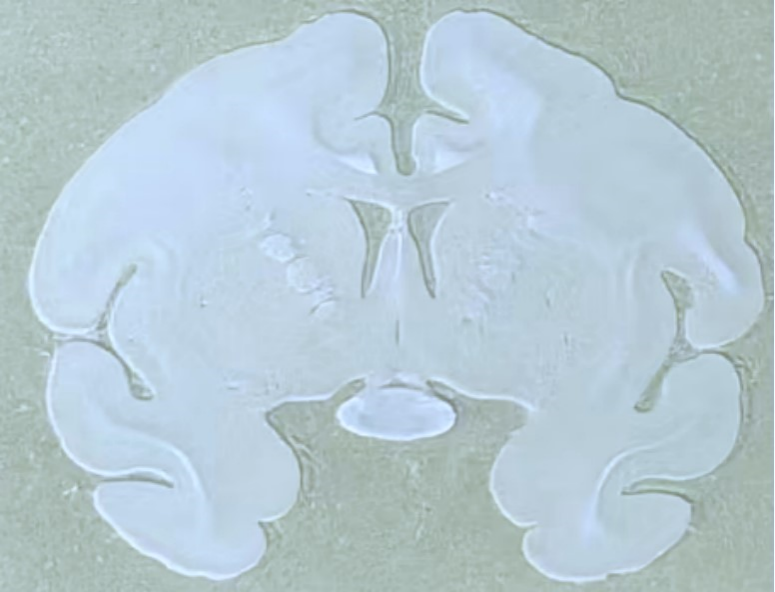

龙迈达斯食蟹猴整脑组织连续切片

猴脑切片是神经科学研究的重要手段,其核心目的可分为:揭示神经疾病机制、评估实验干预效果、推动技术开发与转化。然而相较于啮齿类动物脑组织,猴脑组织体积更大、结构更复杂、质地更软且不均匀,对其进行完整、精准且能良好保持形态的切片,是一项极

具挑战性的技术,往往需要经历一个持续的、精细化的摸索过程。

这一过程的核心在于不断优化:从前处理(如固定时间与渗透的均一性、脱水、包埋介质的选择以兼顾硬度与韧性),到切片设备与参数,每一个环节都可能显著影响切片效果。

对切片方位精度和厚度均匀性要求极高。包括针对后续尼氏染色过程中会出现的脱片情况,我们不断地改进实验条件和方法。

每一次尝试都是宝贵的经验积累,经过近一年这种反复的实践、观察、分析与改进,我公司最终顺利完成食蟹猴整脑连续切片约6000张,形成了猴脑整脑切片技术的操作流程,实现了国际少有的病理技术突破。

白片.png

石蜡切片

尼氏染色.png

尼氏染色